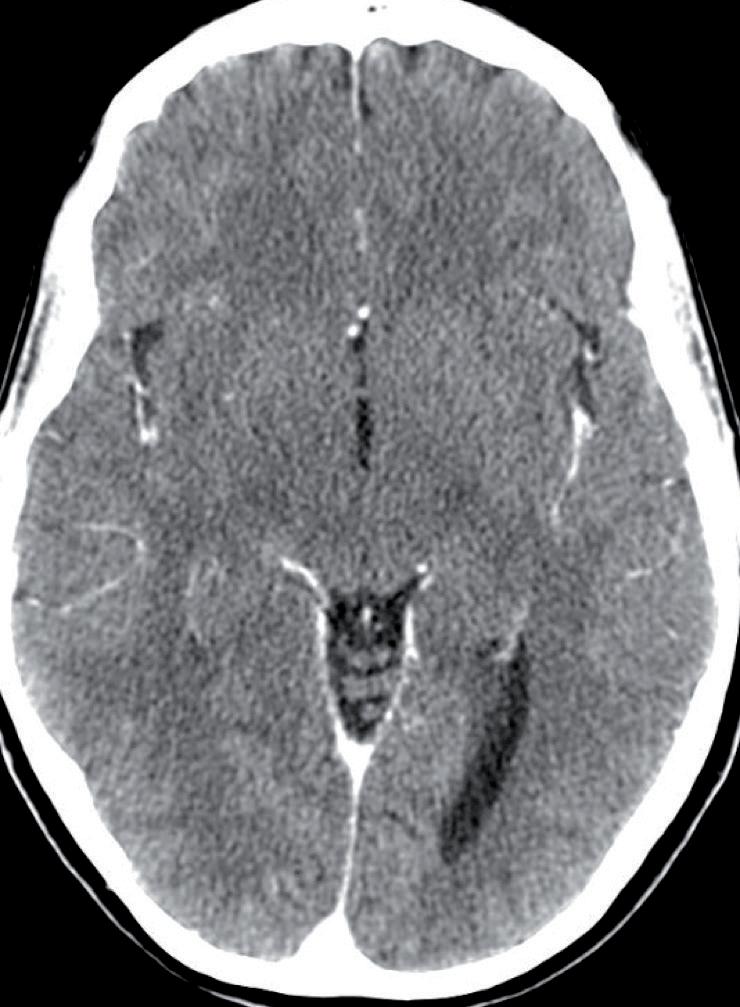

Tuttavia, nonostante la buona risposta iniziale, la TC total body con mezzo di contrasto del 28/12/2023 (figura 1) evidenzia progressione epatica ed encefalica con un quadro radiologico che mostra sovvertimento encefalico diffuso caratterizzato da numerose lesioni secondarie (almeno 10) a netta impregnazione contrastografica a sede sia cerebrale che cerebellare, prevalentemente subcentimetriche, la maggiore di 13 mm in nucleo-capsulare sx con nucleo necrotico e modesto alone edemigeno perilesionale.

La paziente, asintomatica sul piano neurologico e con marcatori tumorali negativi, viene sottoposta previo consulto multidisciplinare, a radioterapia panencefalica con risparmio dell’ippocampo con tecnica IMRT (30 Gy in 10 frazioni) e candidata poi a trattamento di II linea con T-DXd (5,4 mg/kg) q21, supportati dai dati di efficacia riportati dal DESTINY-Breast03, dalle analisi di sottogruppo degli studi DESTINY-Breast01, -02, -03 e dagli incoraggianti risultati preliminari degli studi DEBBRAH e TUXEDO-1.

La rivalutazione strumentale effettuata dopo 4 cicli di trattamento (figura 2) ha mostrato risposta intracranica completa ed epatica parziale. Lo studio della regione mammaria e ascellare con ecografia mammaria e mammografia ha mostrato assenza di lesioni infiltrative con presenza in sede retroareolare sx di un cluster di microcalcificazioni in assenza di linfoadenopatie ascellari. Lo studio tomografico con finestra per osso ha confermato la sovrapponibilità delle lesioni ossee rispetto alla precedente TC, in assenza di fratture patologiche. La paziente tuttora non ha mai manifestato eventi scheletrici secondari né riferisce dolore.